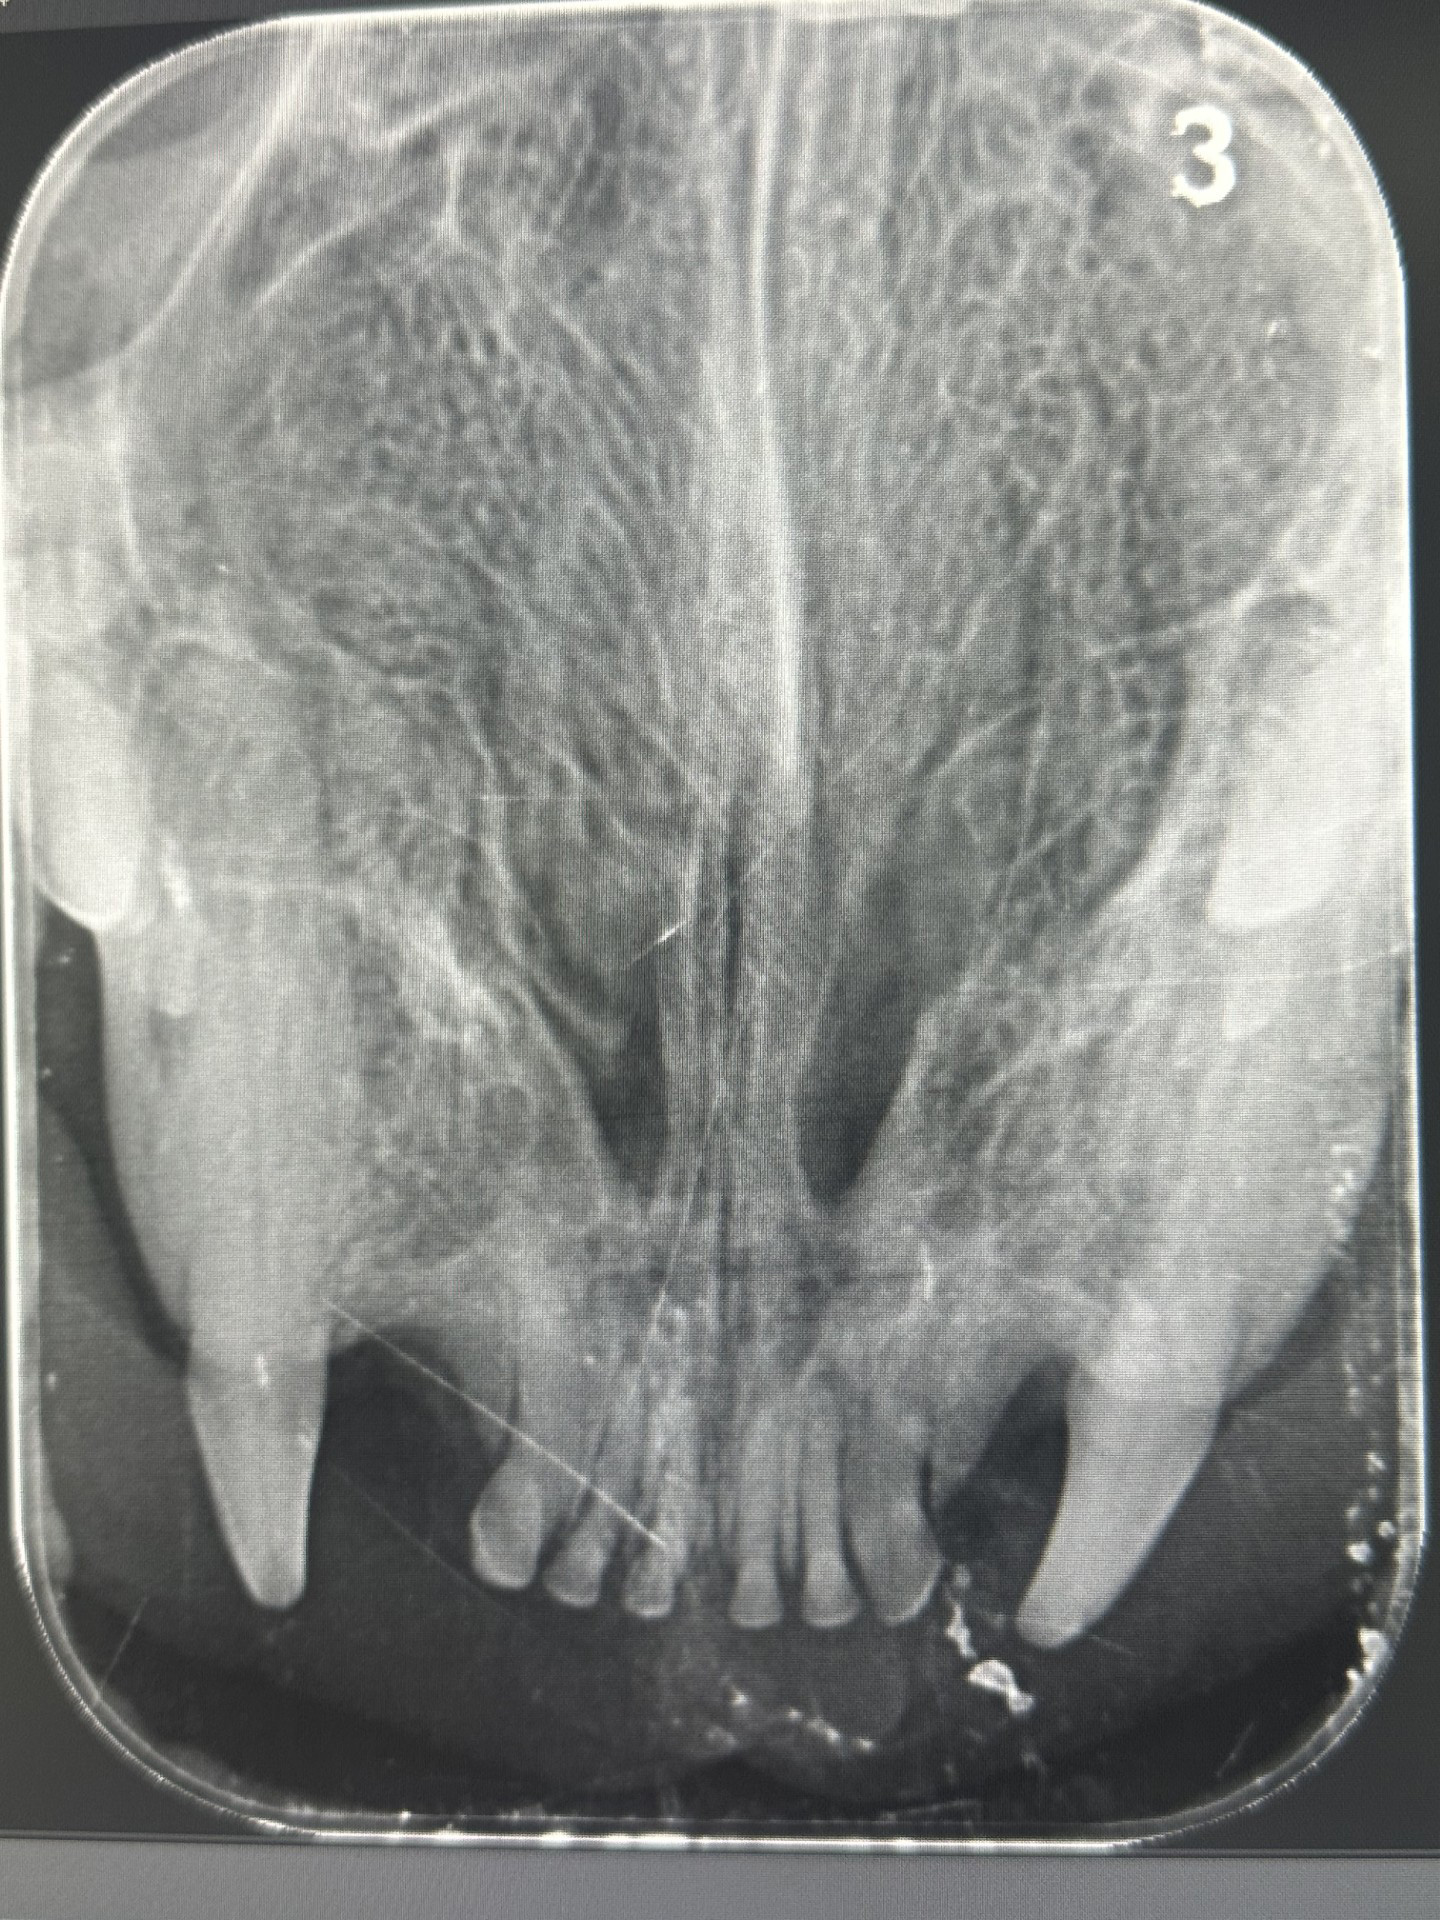

Dental Radiography

Digital dental X-Ray is critical for diagnosing underlying pathology hidden below the gum line.